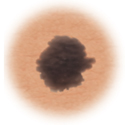

Normal mole.